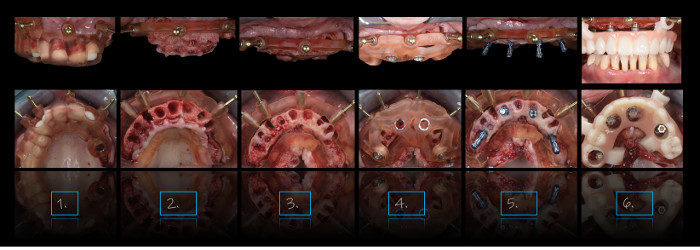

Sistema Smile in a Box de arcada completa. (Imagem: Ricardo Mitrani)

O conceito Smile in a Box tem vários atributos que podem aprimorar a experiência de tratamento do paciente. Ele permite que a equipe de tratamento analise e discuta as várias etapas que a terapia envolve em profundidade. Ele também garante que todas as peças e peças necessárias para realizar esses procedimentos sejam cuidadosamente selecionadas e solicitadas, incluindo uma restauração provisória gerada por CAD / CAM. Portanto, é uma adição bastante pragmática à nossa coleção interdisciplinar de recursos.

Cirurgia de arcada completa utilizando o sistema Smile in a Box. (Imagem: Ricardo Mitrani)